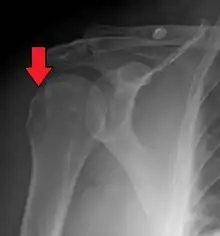

A Hill–Sachs lesion, or Hill–Sachs fracture, is a cortical depression in the posterolateral head of the humerus. It results from forceful impaction of the humeral head against the anteroinferior glenoid rim when the shoulder is dislocated anteriorly.

| Anterior shoulder dislocation on X-ray with a large Hill–Sachs lesion | |

Diagnosis can be suspected by history and physical examination which is usually followed by imaging. Because of the mechanism of injury, apprehension of anterior dislocation is common with provocative maneuvers. Hill–Sachs lesions have been classified as "engaging" or "non-engaging", with engaging lesions defined by the ability of the glenoid to sublux into the humeral head defect during abduction and external rotation. Engaging dislocations have a higher risk of recurrent anterior dislocation, and their presence can help guide surgical management.[2] Imaging diagnosis conventionally begins with plain film radiography. Generally, anteroposterior (AP) radiographs of the shoulder with the arm in internal rotation offer the best yield while axillary views and AP radiographs with external rotation tend to obscure the defect. However, pain and tenderness in the injured joint make appropriate positioning difficult and in a recent study of plain film x-ray for Hill–Sachs lesions, the sensitivity was only about 20%. i.e. the finding was not visible on plain film x-ray about 80% of the time.[3]

The incidence of Hill–Sachs lesion is not known with certainty. It has been reported to be present in 40% to 90% of patients presenting with anterior shoulder instability, that is subluxation or dislocation.[8][9] In those who have recurrent events, it may be as high as 100%.[10] Its presence is a specific sign of dislocation and can thus be used as an indicator that dislocation has occurred even if the joint has since regained its normal alignment. Large, engaging Hill-Sachs fractures can contribute to shoulder instability and will often cause painful clicking, catching, or popping. The average depth of Hill–Sachs lesion has been reported as 4.1 mm.[11]